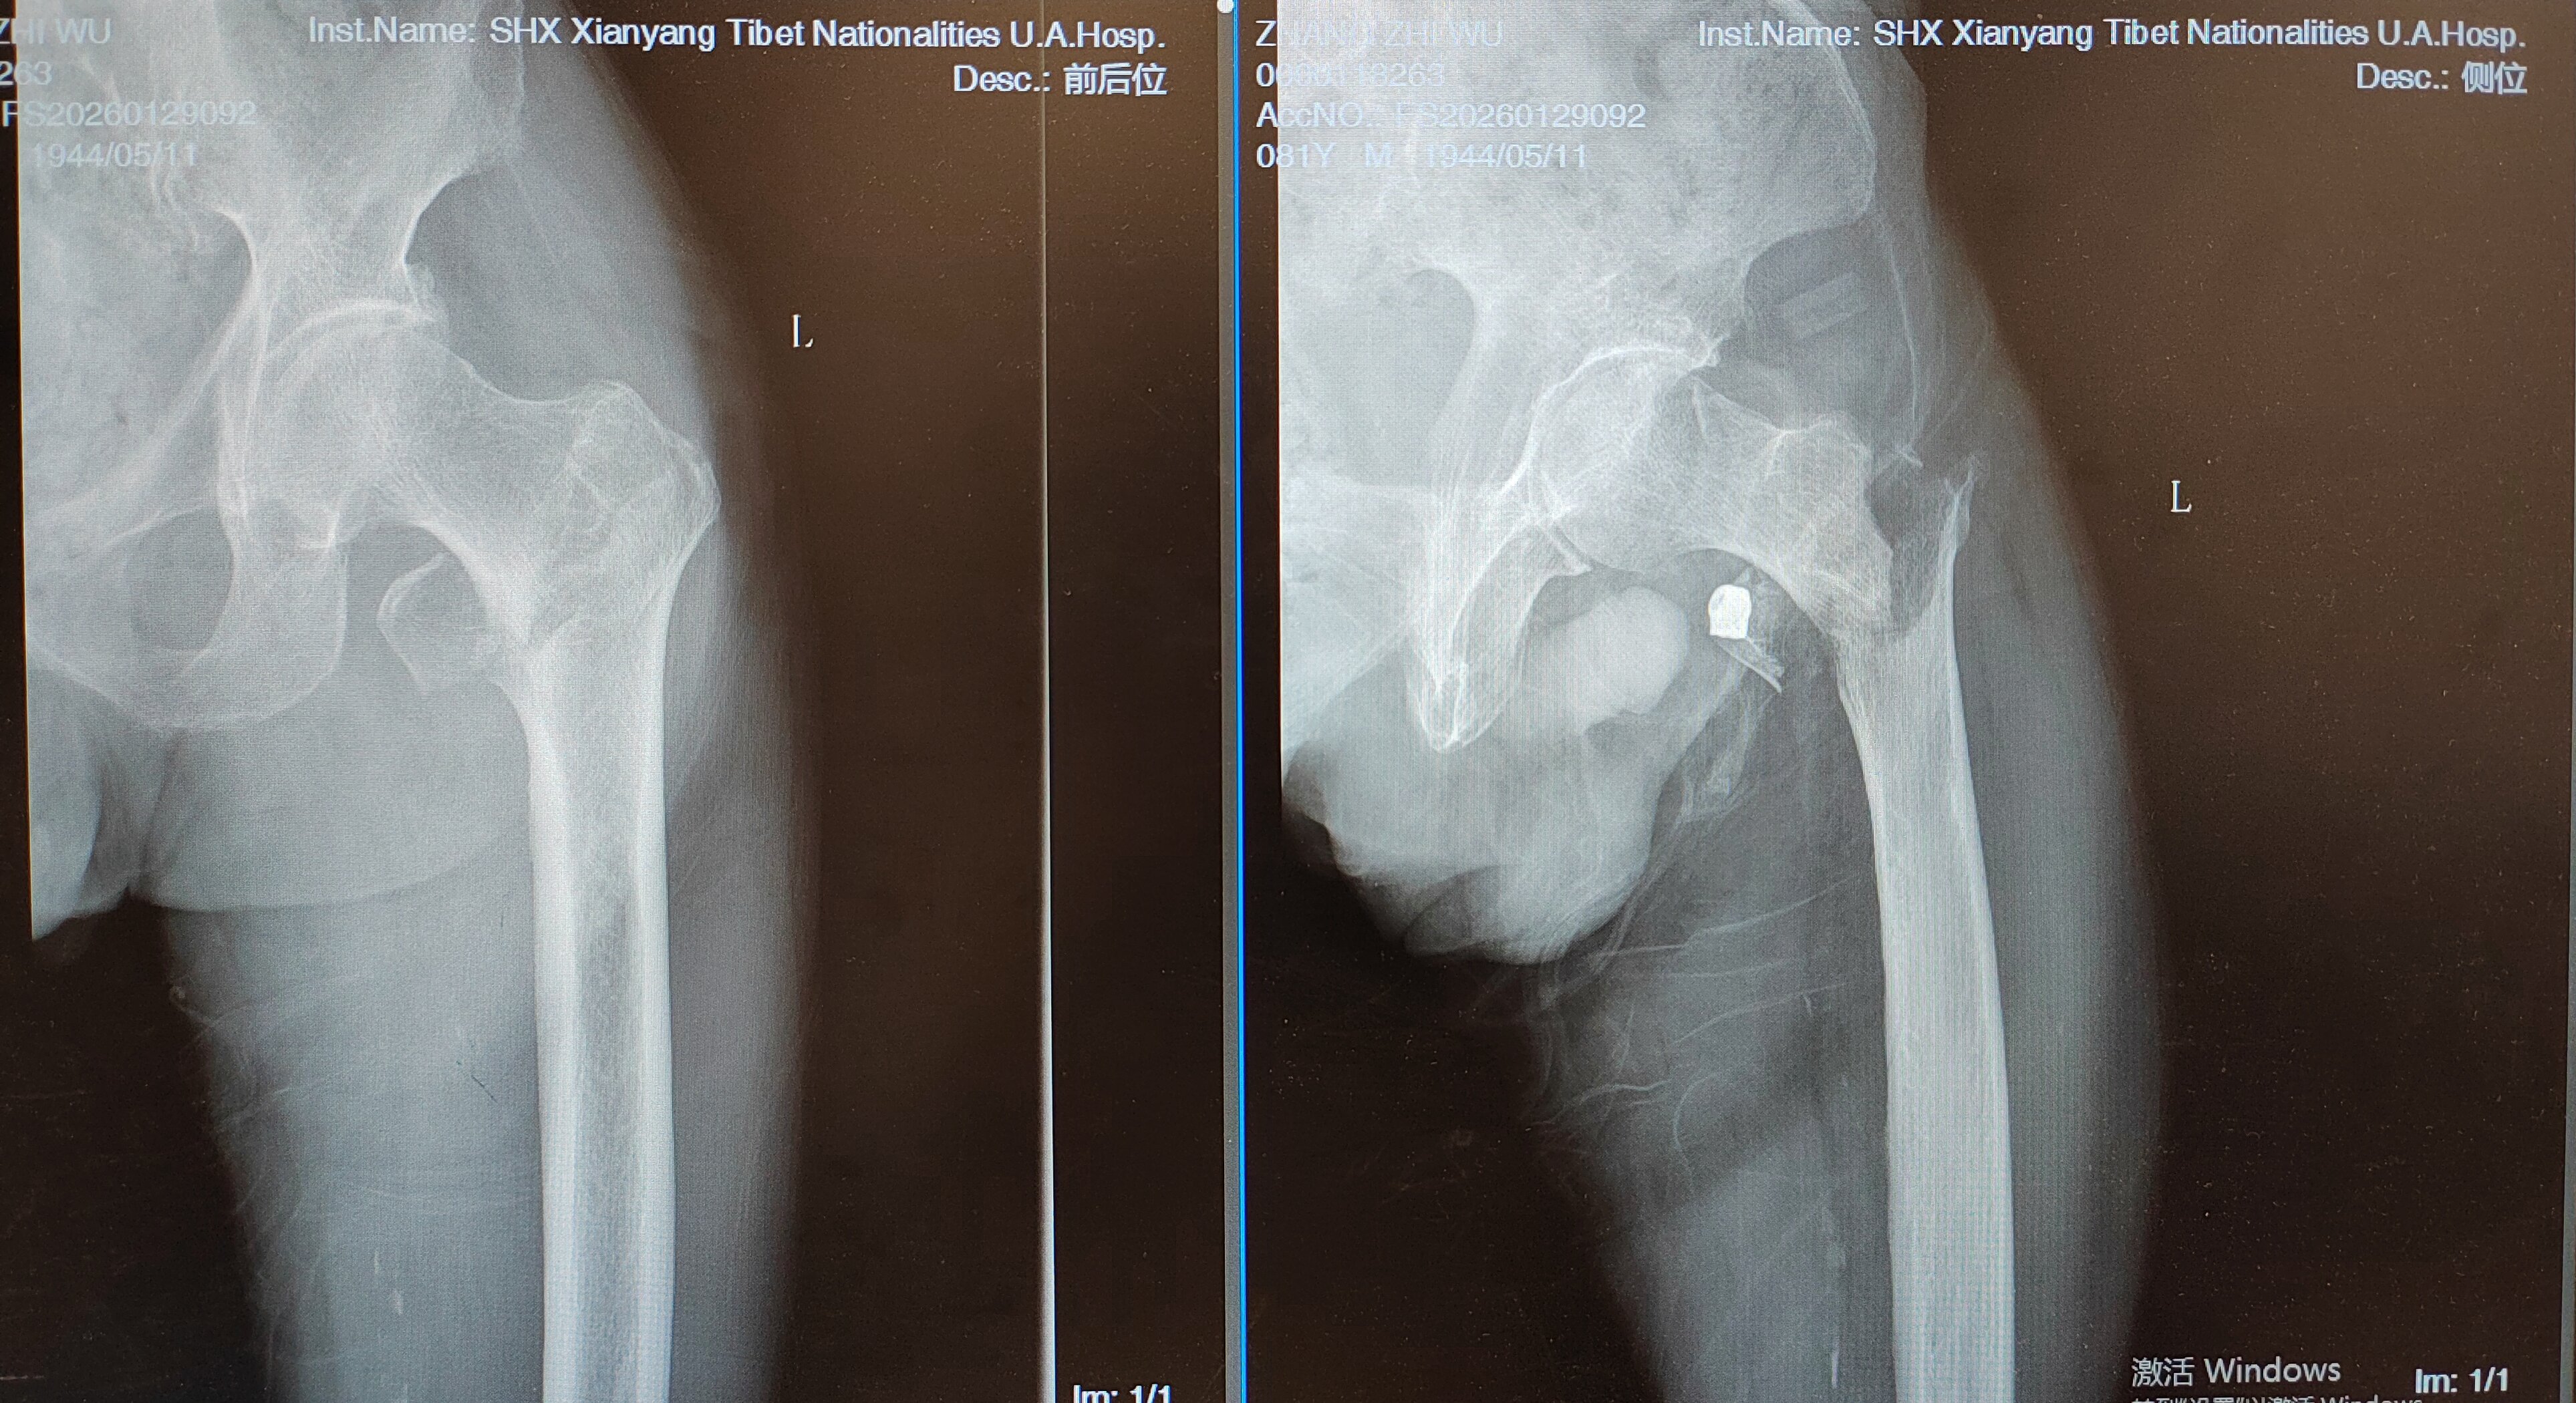

2026年1月底,81岁的张爷爷行走时不慎摔倒,致左髋部肿痛、活动受限,被紧急送往附属医院骨科就诊。经影像学检查,患者被确诊为左侧股骨转子间粉碎性骨折。具有挑战性的是,患者既往病史极为复杂:20年高血压病、2型糖尿病、腔隙性脑梗死病史,2个半月前刚因急性心肌梗死行心脏冠脉支架植入术,基础病多、身体耐受差,手术与麻醉风险极高。

(患者术前X光片)